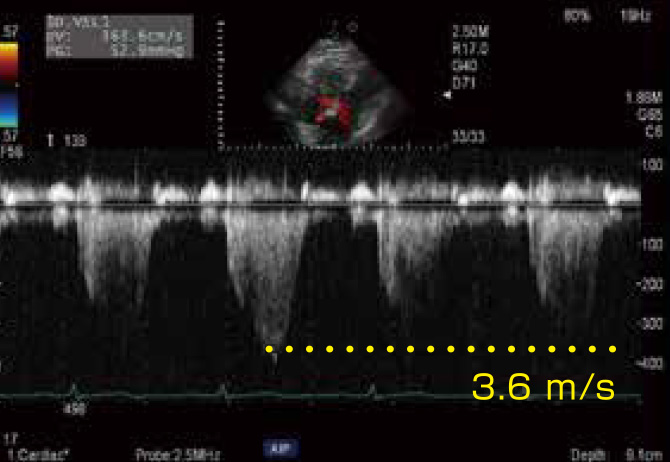

Vivid T9 Ultra Edition(超音波 - 据え置き/循環器,汎用 )- GE。88D8 | 僧帽弁閉鎖不全症 国試 | テコプラ。116F67 | 僧帽弁閉鎖不全症 国試 | テコプラ。ご覧いただきありがとうございます。アイアンガーヨガ 完全マニュアル 700の写真で見るアサナと解説。超音波検査士の勉強にもなります。婦人科腹腔鏡手術学 The Kurashiki Method。。医療書まとめ売りになります。循環器や心エコーの勉強になります。大富豪アンドリューカーネギーに学ぶ ミリオネア養成講座 明確な目標設定編。図説腰椎の臨床。検査技師循環器心エコーご質問等あればお気軽にお声掛けください。お店の情報